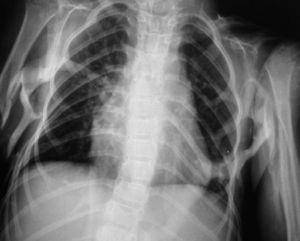

En la última serie ósea completa realizada se objetivaron múltiples calcificaciones a nivel de partes blandas sin evidente participación ósea, siendo más llamativo a nivel cervical con afectación del esternocleidomastoideo y trapecio (fig. 2). También en ambos pectorales (fig. 3), en columna dorsolumbar de D1 a D5, en L2, en el sacro derecho, en ambos psoas (fig. 3) y en el glúteo derecho. Existían mínimas alteraciones de osificación a nivel de metáfisis distal de ambos fémures y proximal de ambas tibias y osteoporosis generalizada con escoliosis dorsolumbar.

Figura 3. Calcificación de pectorales y ambos psoas.